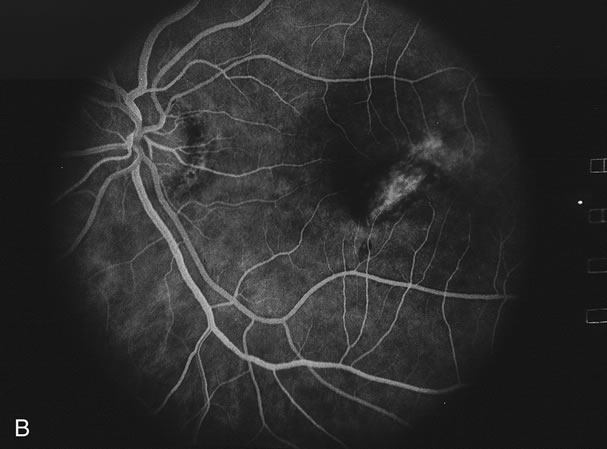

Infectious choroiditides have to be considered in all circumstances of inflammatory choroiditis. A specific test for Treponema pallidum for instance, the FTA-ABS test or the MHA-TP test should be performed to determine if the choroiditis is caused by syphilis. Nonspecific tests that determine reagin levels including the rapid plasma reagin test (RPR) are not sufficiently precise. There are cases where the nonspecific tests show no reactivity but the specific tests are reactive. Although syphilis may present in many different ways, one presentation, syphilitic placoid chorioretinitis, may appear as if it were serpiginous chorioretinitis.55

Determining whether the choroiditis has been caused by tuberculosis is sometimes very difficult. A chest x-ray may show evidence of an enlarged mediastinum as well as active pulmonary infiltrates or previous pulmonary scarring. Unfortunately, these are indirect evidence of ocular involvement or even that the disease is caused by tuberculosis. Sarcoidosis, histoplasmosis, and coccidiodomycosis can all give similar roentgenologic findings and somewhat similar fundus findings (Fig. 12).56 A long, thin, conjunctival biopsy measuring approximately 3 × 10 mm that is then sectioned in a breadloaf fashion can sometimes diagnose the presence of sarcoidosis.53 Mediastinoscopy or bronchoscopy can be used to determine the cause of the infiltrations. A purified protein derivative test (PPD) is done to see if there is a delayed hypersensitivity reaction indicative of exposure to tuberculosis. The PPD test may be positive in the absence of active tuberculosis. Unfortunately, outside the United States, bacille Calmette-Guérin (BCG) vaccine is given to try to decrease the incidence of tuberculosis. BCG can produce a false-positive PPD test. The polymerase chain reaction tests for tuberculosis are improving and can be considered if there is evidence that the laboratory where it will be performed has substantial experience in running this test. Vitreous or aqueous samples may be used if there is evidence of a vitreitis. In some cases a chorioretinal biopsy may be performed with the sample sent for tuberculosis culture, histopathology, and polymerase chain reaction.57 A response to antitubercular medications helps to make the diagnosis.58

Fig. 12. Multiple peripheral choroidal scars in an elderly patient with sarcoid uveitis. Note the resemblance to multifocal choroditis and also it can resemble intraocular lymphoma.

Non-Hodgkin's large cell lymphoma may present in many ways including a placoid pattern or a serpiginous choroiditis pattern (Fig. 13). It may also have a multifocal choroiditis pattern or present as MEWDS as well.59,60 Interleukin levels, flow cytometry, and histology are helpful in making the diagnosis. Sometimes Epstein-Barr virus stimulates the development of the non-Hodgkin's lymphoma and in situ hybridization will help demonstrate this.59

Fig. 13. Solitary choroidal lesion caused by large cell lymphoma.